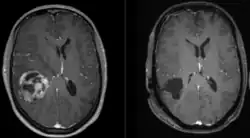

Sagittal MRI with contrast of a glioblastoma WHO grade 4 in a 15-year-old boy

When viewed with MRI, glioblastomas often appear as ring-enhancing lesions. The appearance is not specific, however, as other lesions such as abscess, metastasis, tumefactive multiple sclerosis, and other entities may have a similar appearance.[61] Definitive diagnosis of a suspected GBM on CT or MRI requires a stereotactic biopsy or a craniotomy with tumor resection and pathologic confirmation. Because the tumor grade is based upon the most malignant portion of the tumor, biopsy or subtotal tumor resection can result in undergrading of the lesion. Imaging of tumor blood flow using perfusion MRI and measuring tumor metabolite concentration with MR spectroscopy may add diagnostic value to standard MRI in select cases by showing increased relative cerebral blood volume and increased choline peak, respectively, but pathology remains the gold standard for diagnosis and molecular characterization.

Glioblastoma pre (left) and post (right) resection.

Surgery is the first stage of treatment of glioblastoma. An average GBM tumor contains 1011 cells, which is on average reduced to 109 cells after surgery (a reduction of 99%). Benefits of surgery include resection for a pathological diagnosis, alleviation of symptoms related to mass effect, and potentially removing disease before secondary resistance to radiotherapy and chemotherapy occurs.[67]